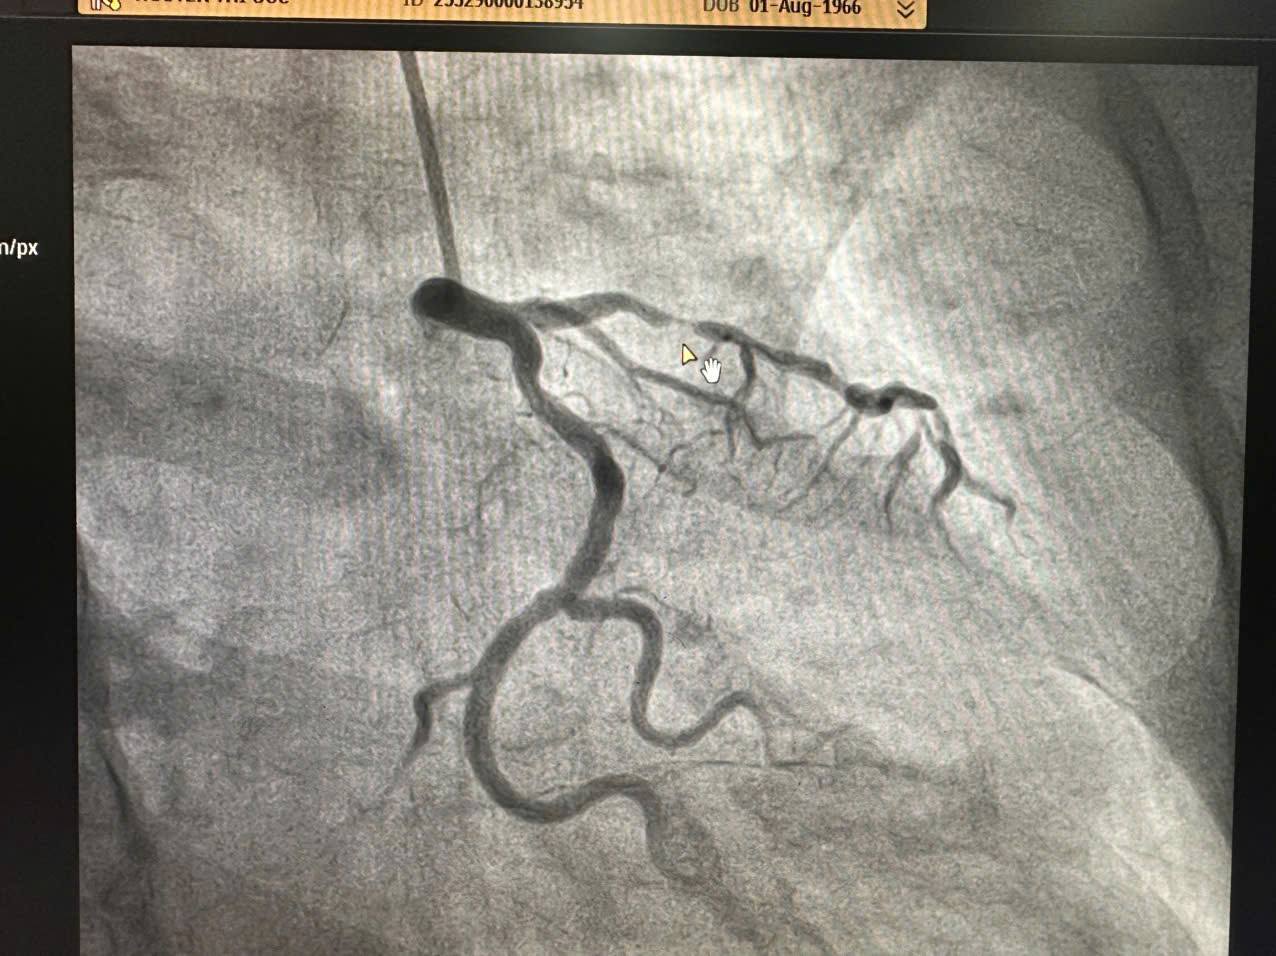

Ca thứ hai – Nhồi máu cơ tim cấp không ST chênh lên

Bệnh nhân nữ, 60 tuổi, nhập viện vì đau ngực kiểu vành.

Xét nghiệm men tim tăng nhanh (12 → 60), chẩn đoán: Nhồi máu cơ tim cấp không ST chênh lên (NSTEMI).

Chụp mạch vành qua da cho thấy tổn thương nặng nhánh động mạch liên thất trước. Ngay sau đó, êkíp can thiệp tiếp tục đặt 01 stent tái tưới máu thành công. Kết quả sau can thiệp: dòng chảy mạch vành được khôi phục tốt, bệnh nhân ổn định và đã chuyển về Khoa Tim mạch điều trị tiếp.